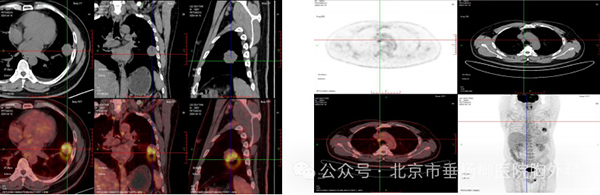

胸外科副主任医师胡晓丹在充分了解患者病情及影像检查后,指示病灶为实性结节且肿物增长过快,需完善全身检查明确有无肿瘤转移可能,后迅速完善全身PET-CT,发现左肺高代谢肿物位于左肺舌段及左下肺内前基底段,病变跨越斜裂胸膜(大小4.6*4.4,SUVmax9.1),恶性可能性大;纵隔、左肺门、右侧内乳区淋巴结转移瘤可能(大者短径1.6cm,SUVmax4.7)。考虑患者淋巴结转移瘤可能性大,需尽快明确病变淋巴结性质,给予经支气管超声内镜纵隔淋巴结穿刺活检术(EBUS-TBNA),胡晓丹会同胸外科医师赵洋乐顺利穿刺4R、4L区、7区、10L淋巴结,术后病理均未见肿瘤细胞,初步考虑淋巴结肿大为良性病变。

术前PET-CT-左肺占位 纵隔淋巴结肿大